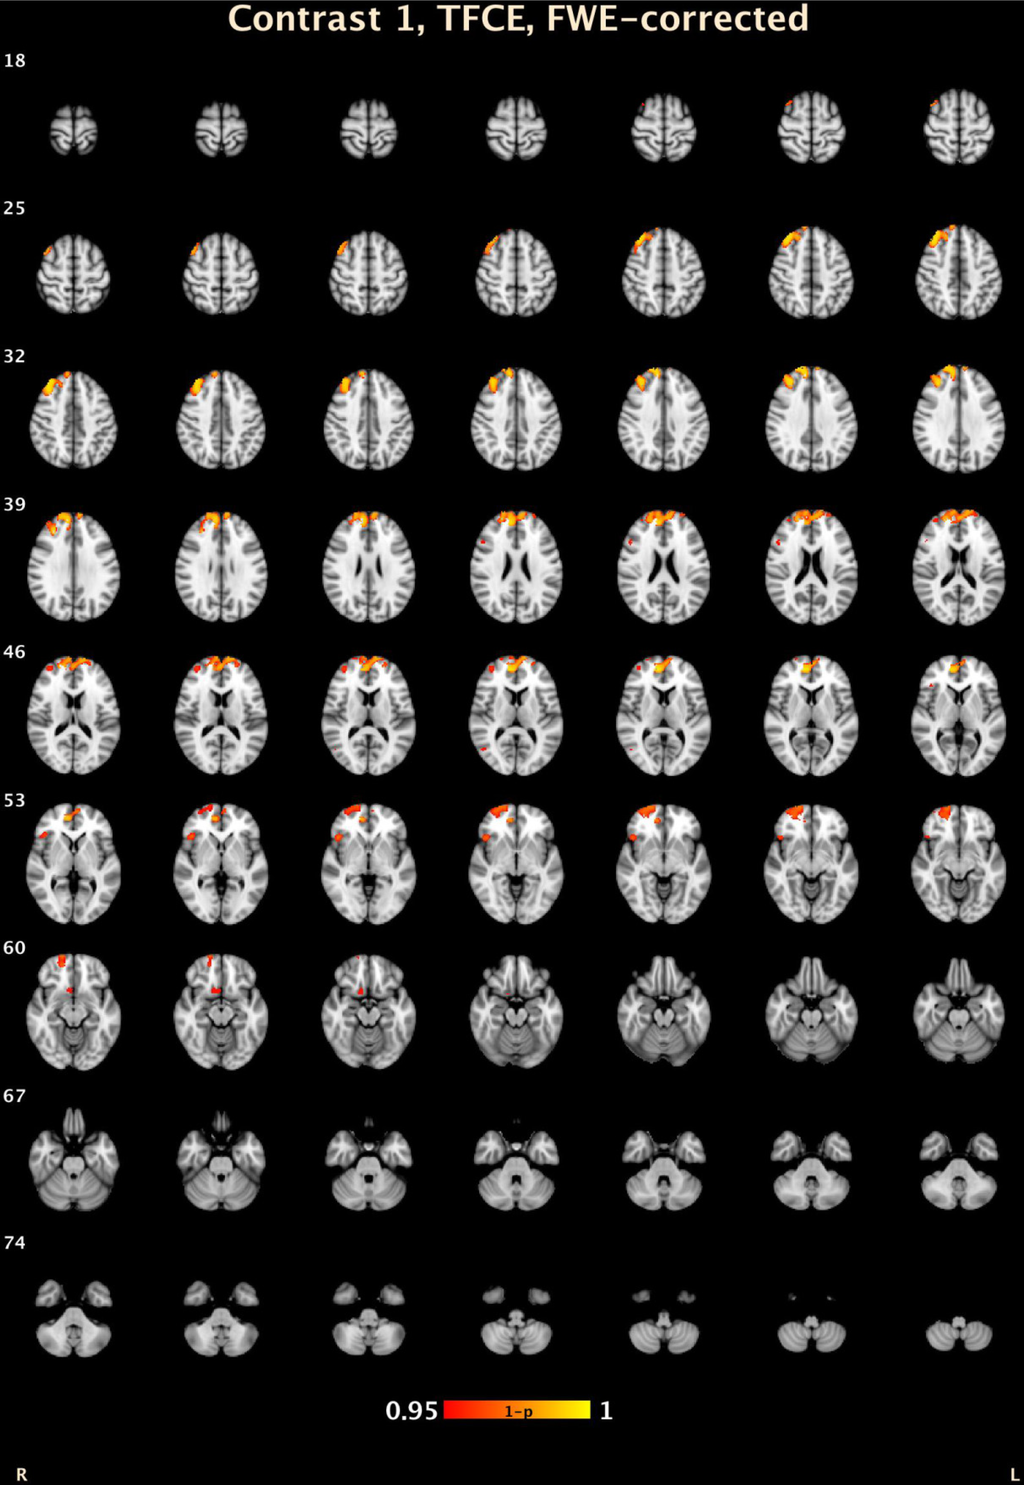

| CD-BD Compared to HC: Voxel Level | |||||||

| 1 | 23 | 0.002 | 10.2 | 51.8 | 8 | R Medial Frontal Gyrus | 10 |

| Threshold-Free Cluster Enhancement | |||||||

| 7 | 3273 | 0.005 | 15.2 | 49.4 | 26.6 | R Medial Frontal Gyrus | 9 |

| 6 | 449 | 0.027 | 23.2 | 60.8 | −6.8 | R Superior Frontal Gyrus | 10 |

| 5 | 135 | 0.031 | 45.2 | 23.4 | −2.6 | R Inferior Frontal Gyrus, B | 47 |

| 4 | 73 | 0.046 | 9 | 14 | −14.4 | R Anterior Cingulate | 25 |

| 3 | 26 | 0.044 | 49.8 | 21.4 | 21.6 | R Middle Frontal Gyrus | 46 |

| 2 | 11 | 0.047 | 49 | −65.6 | 9.8 | R Middle Temporal Gyrus | 37 |

| 1 | 1 | 0.05 | 42 | 24 | −20 | R Inferior Frontal Gyrus, B | 47 |